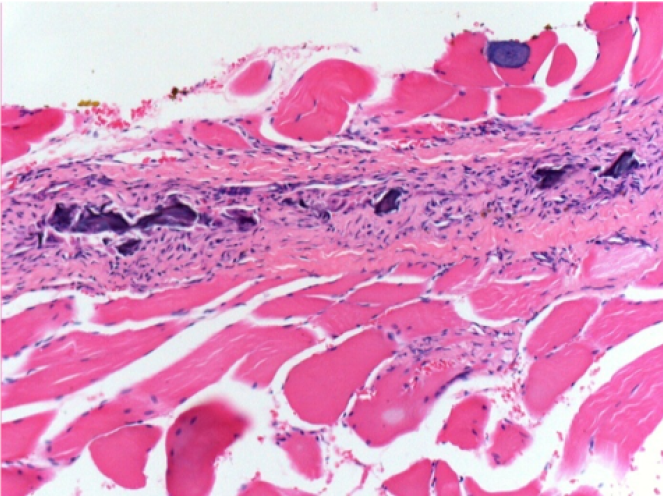

0.5 ml ( 5x 0.1ml) Endopeel SC Injection in the right subcutaneous pretibial area.

L:200x-Control-SC

R-D10-SC-200X